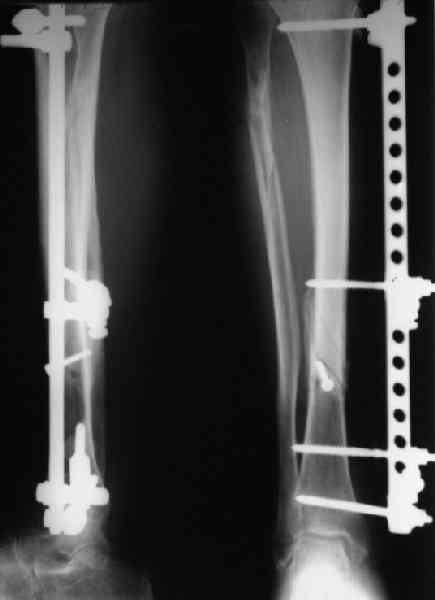

Мы лет 5-6 назад, когда еще не делали закрытое штифтование, сделали с десяток подобных операций, в том числе несколько на бедре. Репозиция закрытая, кортикальный винт 4,5 мм через прокол. Ближний кортекс рассверливали до 5 мм после нарезания резьбы, то есть получался нормальный компрессирующий винт. Аппараты только уже делали монолатеральные стержневые, чтобы не прошивать насквозь мышцы спицами (пример в приложении).

Хотя, конечно, вполне можно и обычные кольца со

спицами.